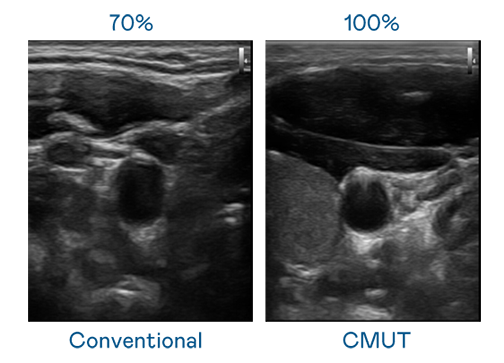

CMUT 技术是一种用电容式微机电元件来产生超音波讯号的技术。与传统 PZT 压电式技术相比,CMUT 频宽增加 30%,更宽频的超音波讯号让影像解析度大幅提升,是实现高影像品质医疗超音波扫描、促进精准医疗发展的关键技术。

超音波影像的解析度高低,首先取决于探头能发出的讯号频宽。IM电竞 CMUT 可提供高清晰的超音波讯号,提供高频宽、高灵敏度、影像纹理细节更高的超音波影像,协助医护人员缩短影像判读时间及利用精准的医疗影像进行诊断。